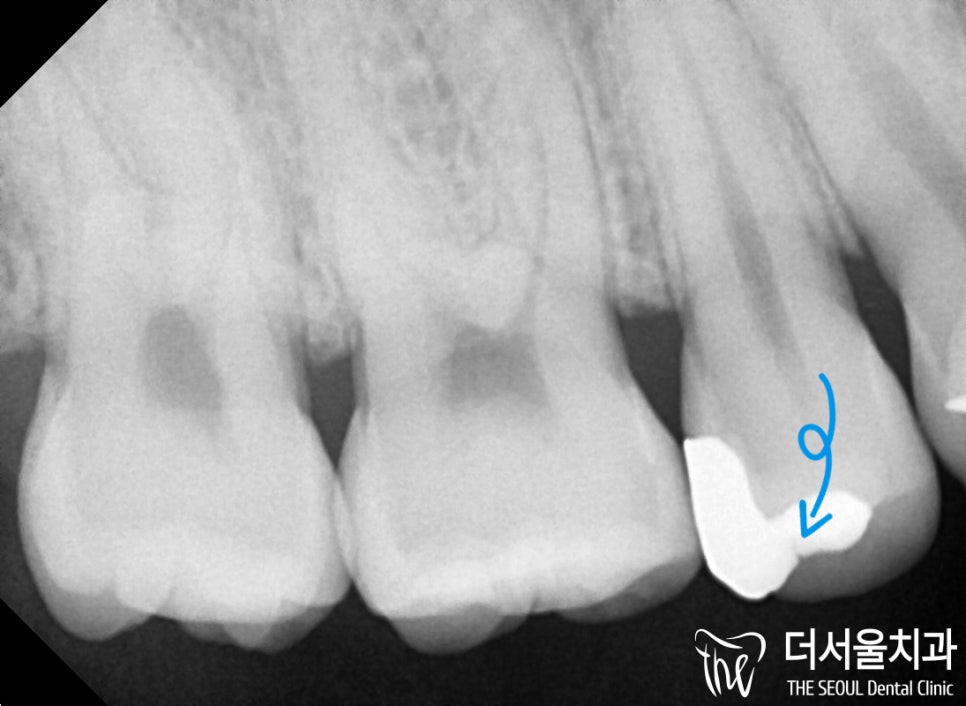

더서울에서는 치근단 사진으로

인레이에 파절이 나타나

2차 우식이 나타난 것까지

확실하게 확인을 한 다음